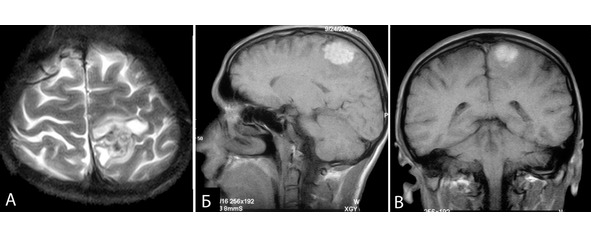

Из анамнеза известно, что эпилептические приступы беспокоят в течение 20 лет. С течением времени отмечалось учащение и нарастание тяжести приступов. К моменту госпитализации приступы беспокоили до нескольких раз в неделю. Характер приступов: 1) ауры продолжительностью 2—3 секунды в виде «наплыва» мыслей и воспоминаний, состояние по типу дереализации затем аутомоторный пароксизм с амнезией события, 2) те же приступы с последующим переходом в генерализованный клонико-тонический припадок. Продолжительность приступа неизвестна, так как пароксизмы амнезирует. Принимал различные антиконвульсанты в дозах не менее средней терапевтической с недостаточным эффектом. При МРТ выявлена кавернома правой височной доли (рисунок 30).

Рисунок 30. Клиническое наблюдение №5, МРТ больного в аксиальной проекции. А – режим Т2. Б – режим Т1.